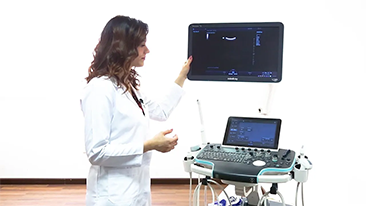

Resona 7

New Waves in Ultrasound Innovation

With Zone Intelligence

Since the company was founded, Mindray has been continuously exploring new ways to improve diagnostic confidence. Powered by the most revolutionary ZONE Sonography? Technology, Resona 7ŌĆÖs new ZST+ platform brings ultrasound image quality to a higher level by zone acquisition and channel data processing.

As well as the premium level image quality, Resona 7 also enhances clinical research capabilities with the revolutionary V Flow for vascular hemodynamic evaluation, and the most intelligent plane acquisition from 3D datasets for fetal CNS diagnosis. Combining the most intuitive gesture-based multi-touch operation and all the essential clinical features, Resona 7 is truly leading new waves in ultrasound innovation.